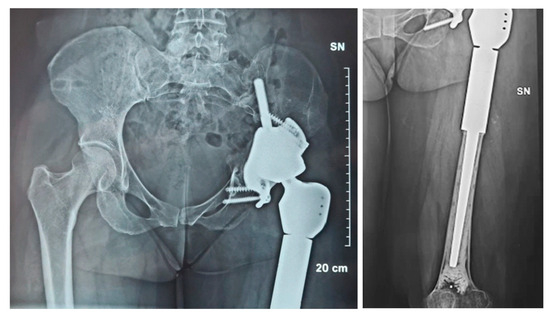

2.1. Case #1